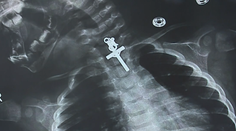

Zaujímavosti Šokujúca snímka z röntgenu. Dieťaťu sa zasekol v pažeráku krucifix Katarína Ács 15. 11. 2023